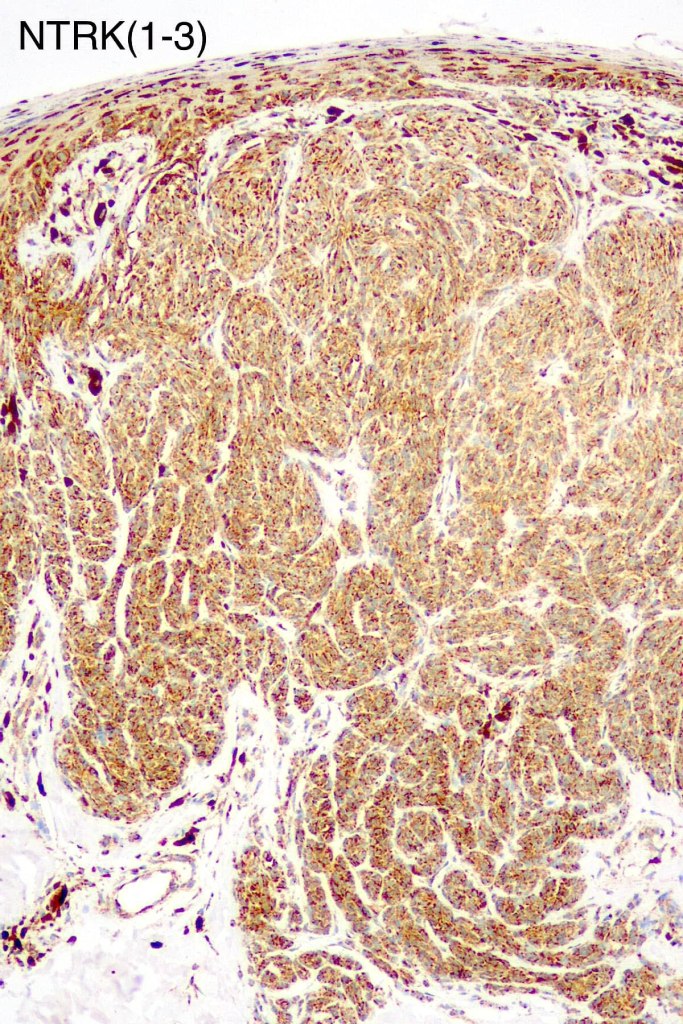

•Spitz nevus has been shown to be associated with receptor tyrosine kinase mutations including ALK, ROS, RET, & NTRK1-3, MET, mutations in HRAS or MAP2Ki, copy number gains of 11p

•S100, MART1 & SOX10 +ve, HMB45 +ve (superficially & lost progressively with depth), p16 +ve, p21 +ve

. BRAF -ve